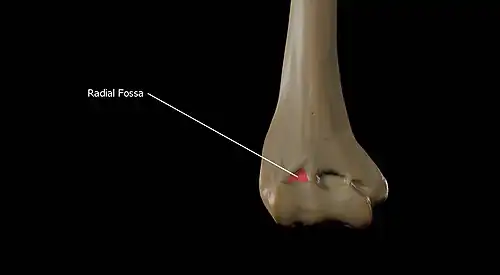

Above the front part of the capitulum is a slight depression, the radial fossa, which receives the anterior border of the head of the radius, when the forearm is flexed.